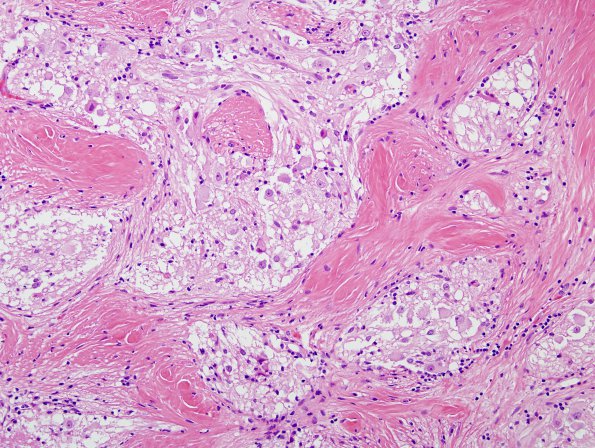

Washington University Experience | NEOPLASMS (NEURONAL) | Ganglioglioma | 21B4 Ganglioglioma (Case 21) H&E 2

In this unusual growth pattern ganglion cells/neurocytes occupy the interstices between bands of glial processes and collagen